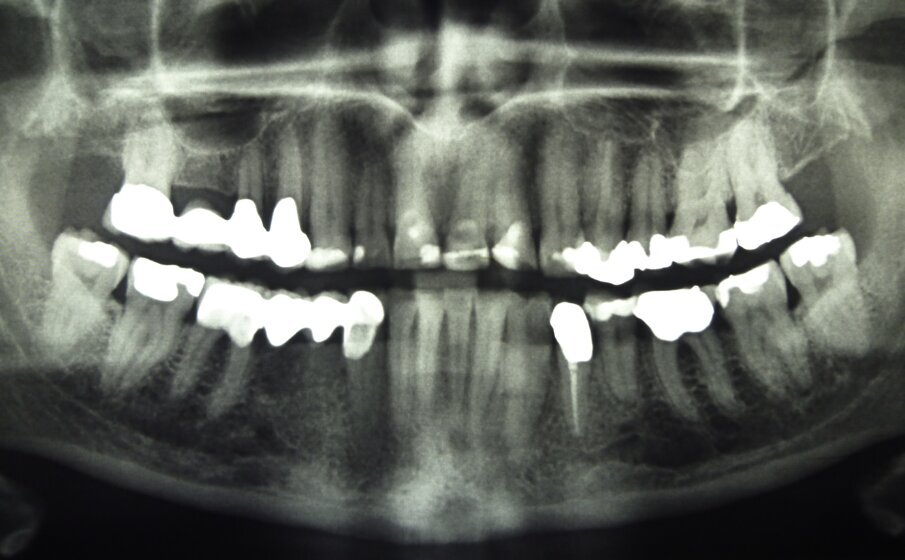

Fig. 2: Radiograph of initial situation

A 55-year-old woman presented at the Department of Preventive Dentistry, Periodontology and Cariology of the University of Göttingen. The clinical and radiological examination revealed an adult dentition that had been insufficiently treated with fillings and dental restorations and exhibited a loss of vertical dimension of occlusion (Figs. 1 and 2). Insufficient restorations (secondary caries) were found on teeth 24, 25, 26, 27, 37, 38, 35, 47, and 48. The existing bridge (17–15, 14) was insufficient due to extensive ceramic fractures. Part of the hard tissue of the upper maxillary incisors with their — sometimes extensive — composite restorations had been lost to attrition and vestibular erosion. The endodontic treatment of tooth 34 was adequate, while tooth 46 required a primary endodontic treatment due to an irreversible pulpitis. All other teeth were vital and free of symptoms. The periodontal findings showed moderate gingivitis (periodontal screening index < 3 in all sextants). Teeth 13, 23, 24, and 43 additionally exhibited vestibular gingival recessions.